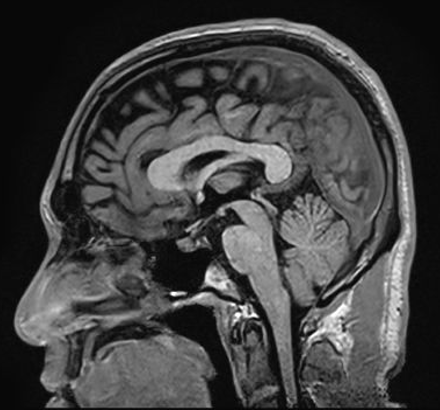

■解剖がクッキリ!『T1強調画像』

まずは「T1強調画像」です。

この画像の特徴は「水が黒く、脂肪が白く映る」こと。

体の構造(解剖)が非常に綺麗に見えるため、「ここは肝臓、ここは筋肉」といった位置関係を把握するのに最適です。

医師が「まずは全体像を把握しよう」という時に、真っ先に見る地図のような役割を果たします。

臨床での使いどころ:脳の解剖構造の把握、造影剤使用後の病変検出、脂肪を含む病変の評価など